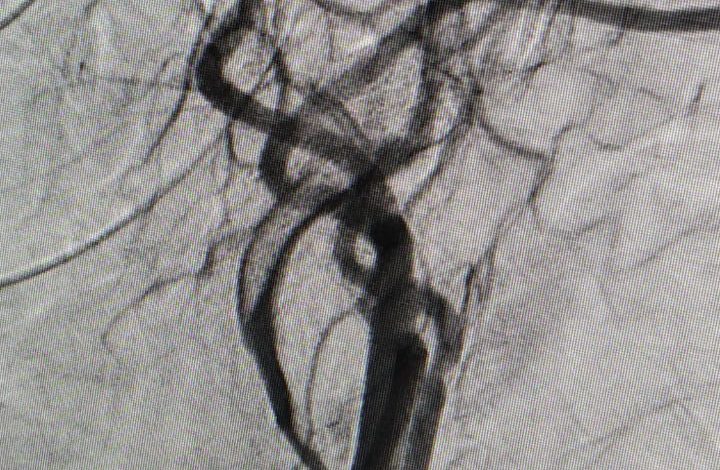

यह व्यक्ति बीमारी के लक्षण आने के छः घंटे के भीतर हॉस्पिटल में पहुँचे और यहाँ पर डीएसए मशीन की मदद से नूरोरेडीआलॉजी की टीम ने आकस्मिक उपचार प्रदान किया और आज मरीज़ पूर्ण तौर पर स्वस्थ है। आईजीएमसी के डॉक्टर्स और मशीन के माध्यम से मरीज की जान बचाई गई है।इस केस को लेकर आईजीएमसी की पीठ थपथपाई जा रही है।